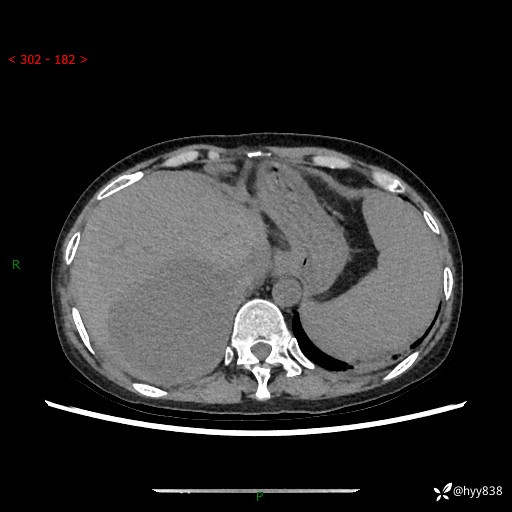

上腹部CT平扫